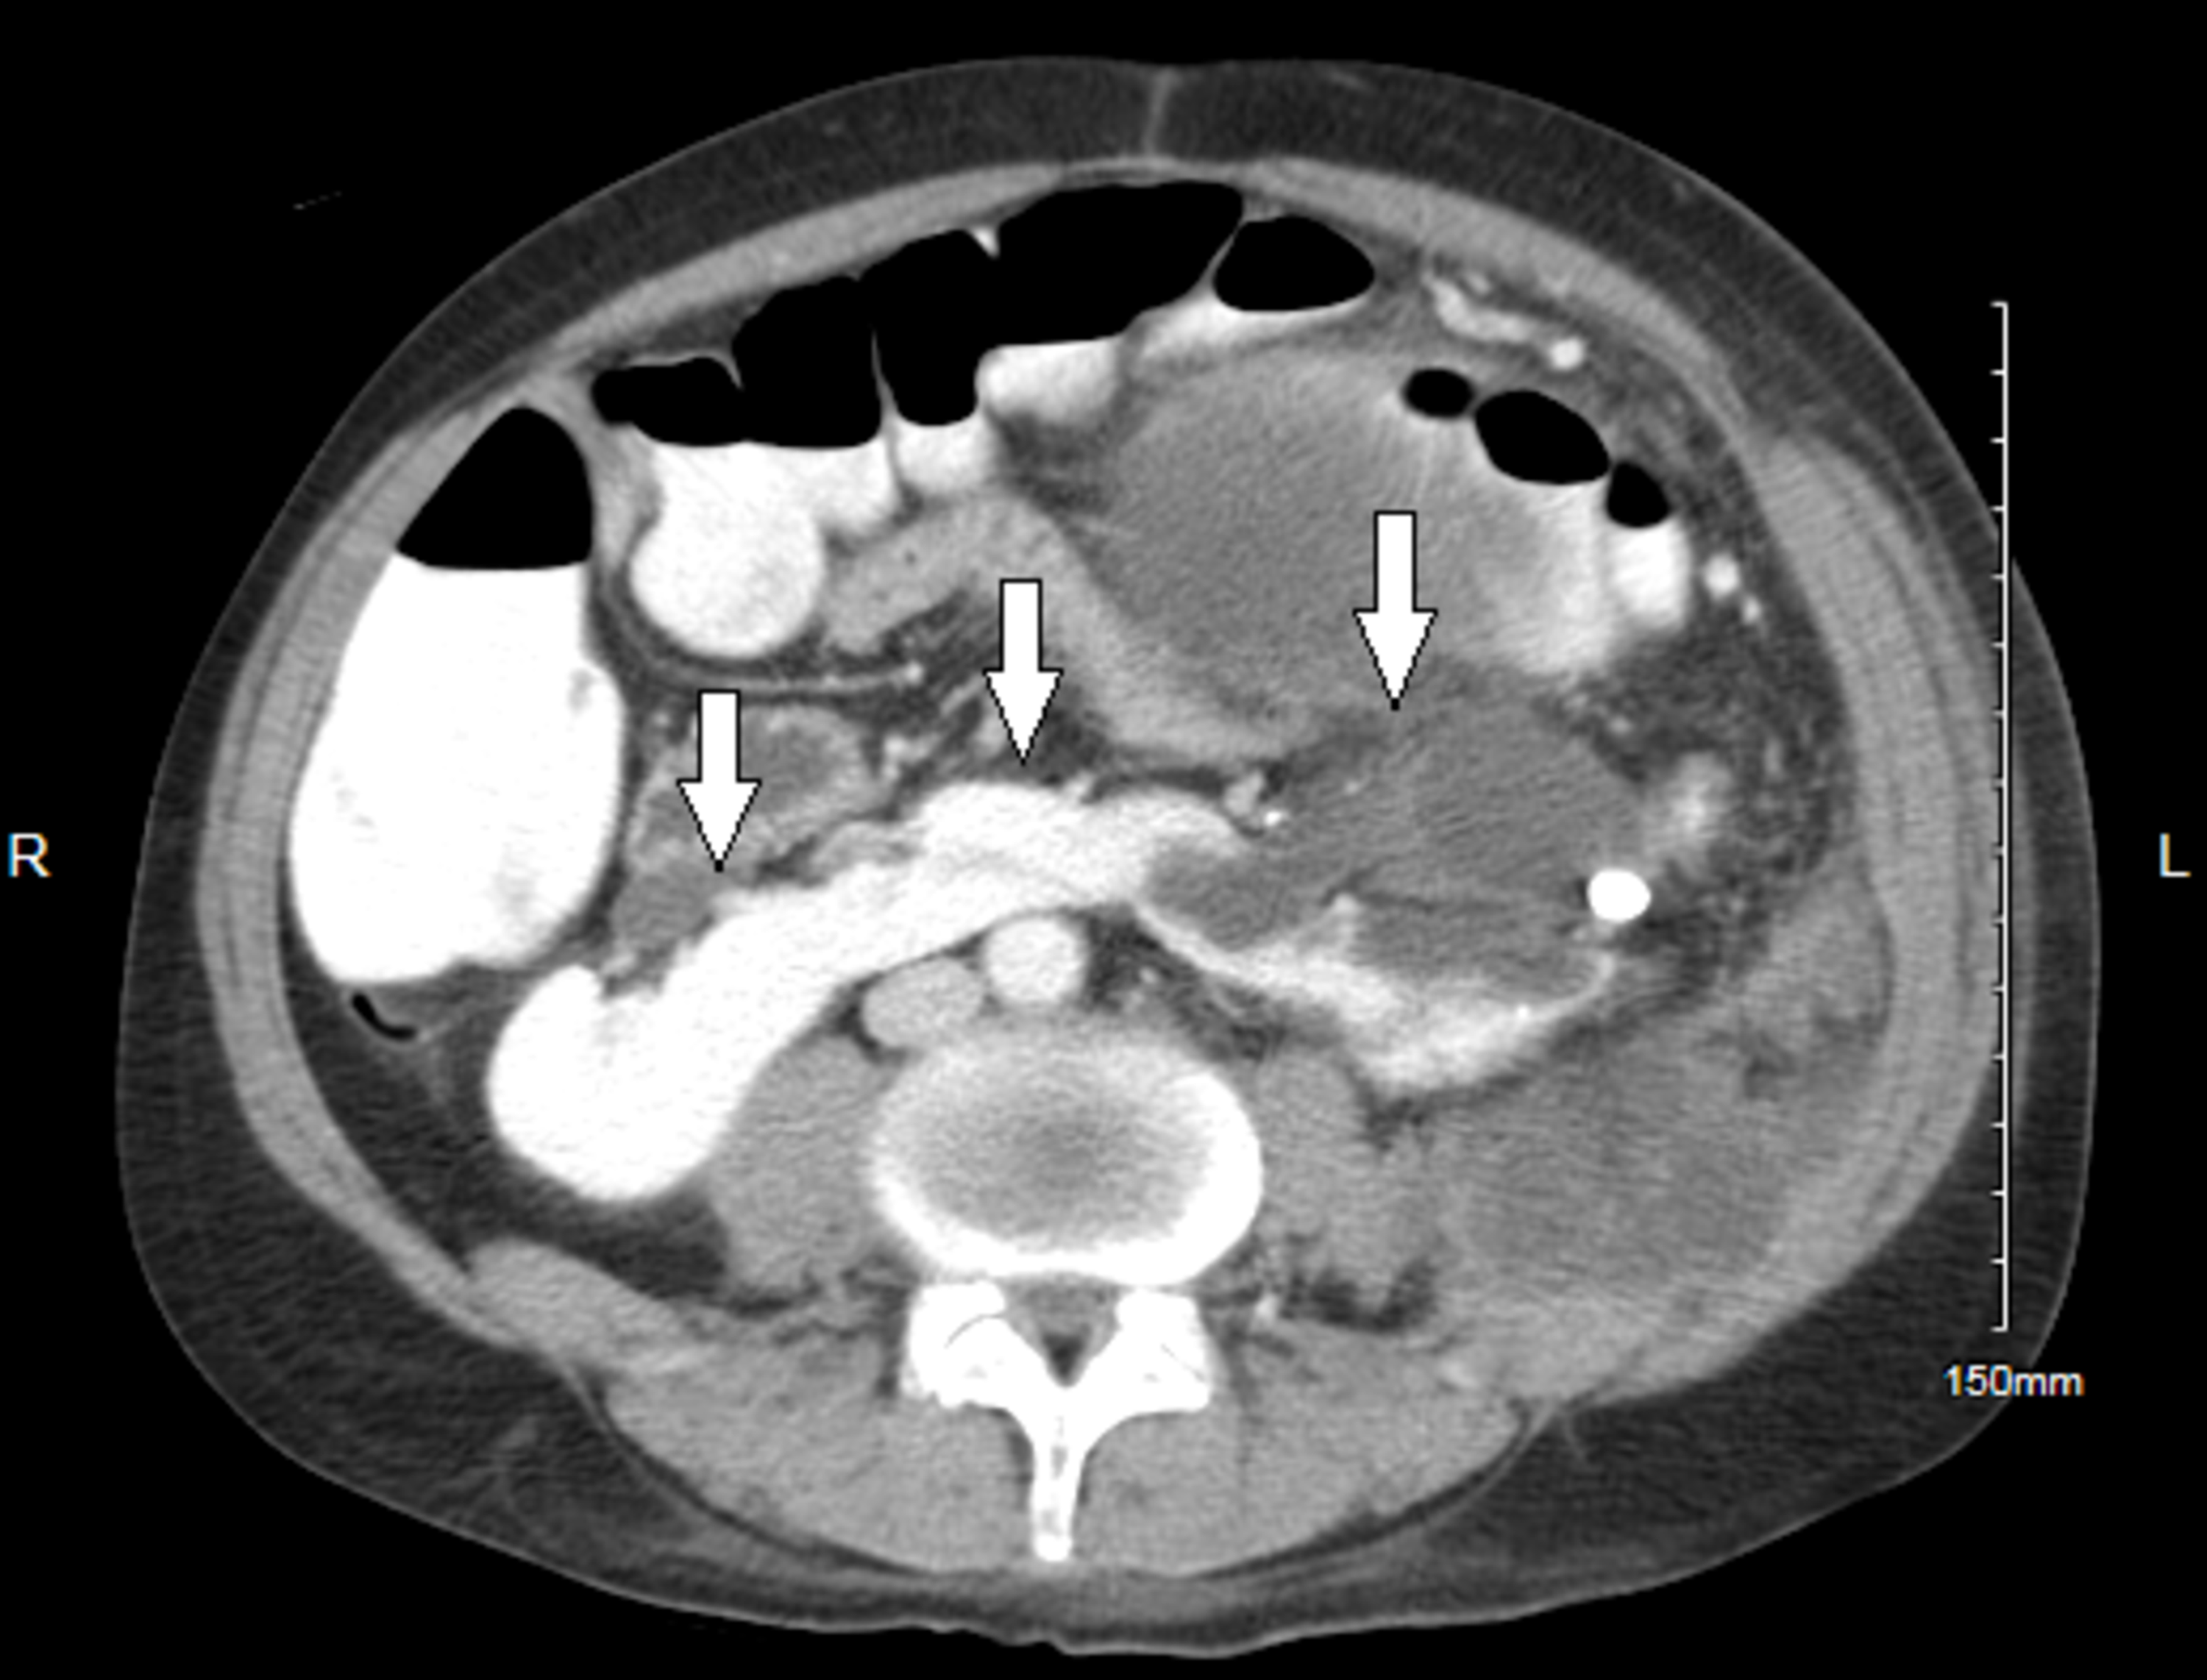

Contrastenhanced abdomen selected axial image horseshoe kidney, the

Contrastenhanced abdomen selected axial image horseshoe kidney, the Horseshoe Kidney Cancer We report a case of clear cell rcc in a horseshoe kidney. Horseshoe kidney is one of the most common congenital renal fusion anomalies and the incidence of renal cell carcinoma in. To contrast surgical outcomes of horseshoe kidney (hsk) patients with localized renal masses suspected of cancer with. Computed tomography scan revealed a horseshoe kidney anomaly. To contrast surgical. Horseshoe Kidney Cancer.